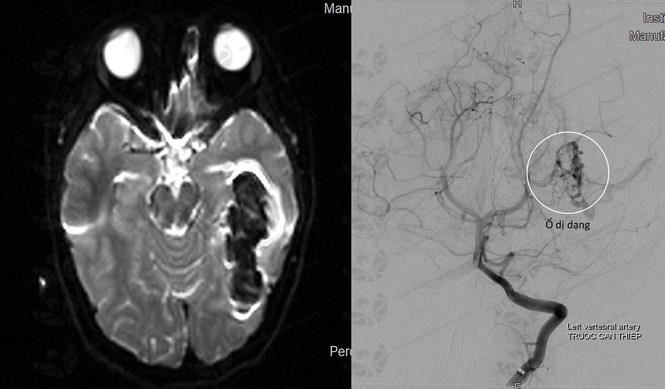

Đến SIS Cần Thơ, bé N được đưa vào kiểm tra tìm ra nguyên nhân gây đột quỵ xuất huyết não, sau khi hội chẩn các bác sĩ rút ra kết luận bé bị dị dạng mạch máu não bẩm sinh, phương pháp điều trị tốt nhất cho BN lúc này là can thiệp nội mạch bằng công nghệ DSA. Sau khi được can thiệp, bé N tỉnh, da niêm hồng.

TS.BS Trần Chí Cường, Giám đốc BV Đa khoa Quốc tế SIS Cần Thơ chia sẻ, đột quỵ ở trẻ em phần lớn là xuất huyết não; nguyên nhân do vỡ dị dạng mạch máu bẩm sinh và không có bất kỳ triệu chứng nào hoặc một số ít có biểu hiện đau đầu, co giật, động kinh.

“Khi xảy ra đột quỵ ở trẻ em, thì ngày nay sẽ điều trị theo phương pháp can thiệp nội mạch DSA, ít xâm lấn. Đặc biệt là điều trị được những vùng não sâu mà phẫu thuật không mổ tới. Ngoài ra sau can thiệp trẻ nhỏ bảo tồn được phần lớn chức năng, không để lại bất kỳ vết sẹo nào. Khác với phẩu thuật mổ hở hồi trước, việc phẫu thuật để lại di chứng nặng nề, ảnh hưởng đến thẩm mỹ, thậm chí là tổn thương tâm lý đến các bé còn nhỏ tuổi” – BS Cường cho biết.

Vì vậy khi trẻ có triệu chứng đau đầu, co giật, động kinh… cần sớm cho trẻ đi tầm soát và để tầm soát tốt mạch máu não cho trẻ, không gây ảnh hưởng đến sức khoẻ. MRI 3 Tesla sử dụng từ trường (lực hút nam châm) là thiết bị tầm soát an toàn nhất, đưa ra hình ảnh rõ nét sớm phát hiện các dị dạng mạch máu để kịp thời điều trị ngăn ngừa đột quỵ.